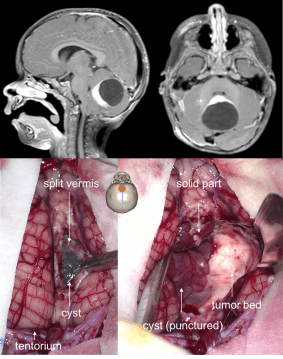

la tumeur est souvent kystique, se clive bien du cervelet adjacent, la paroi du kyste peut contenir du tissu tumoral ou non.

elle est avant tout chirurgicale, que ce soit :

- pour la résection tumorale

dans quelques cas (tumeurs de découverte fortuite, dans la NF1, récidive de faible volume), la neuronavigation peut être utile car la tumeur est petite.

l’examen histo-pathologique extemporané est souvent utile, car si la tumeur infiltre des régions délicates (pédoncule cérébelleux, V4), il est préférable que l’exérèse reste incomplète.